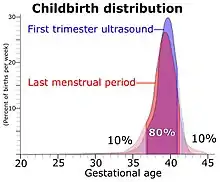

Furthermore, actual childbirth has only a certain probability of occurring within the limits of the estimated due date. A study of singleton live births came to the result that childbirth has a standard deviation of 14 days when gestational age is estimated by first trimester ultrasound, and 16 days when estimated directly by last menstrual period.[32]